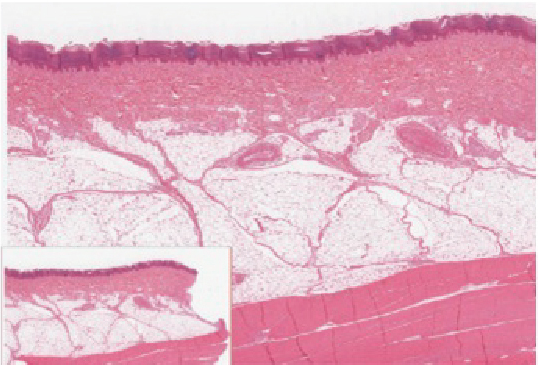

Image of thin skin and thick skin

Figure 4.1.2. Thin skin versus thick skin. These images show cross-sections of the epidermis and dermis of (a) thin and (b) thick skin. Note the significant difference in the thickness of the epithelial layer of the thick skin. From top, LM × 40, LM × 40. (Micrographs provided by the Regents of University of Michigan Medical School © 2012).